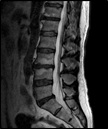

- Resonancia Magnética Nuclear (RM)

Es una prueba no invasiva y que no utiliza tecnología de radiaciones ionizantes (solo emite un campo electromagnético) por lo que se considera inocua. Tiene una alta sensibilidad y especificidad sobre todo en el diagnóstico de lesiones de tejidos blandos (no del hueso), como por ejemplo, las hernias discales, infecciones, tumores, etc.

Es la prueba que mejor permite ver esos tejidos blandos. Sin embargo, tiene el problema de tener muchos falsos positivos. Es decir, ve lesiones que no se traducen en enfermedades y puede confundir en el diagnóstico y llevarnos a realizar tratamientos agresivos no necesarios. Realizar una resonancia cuando no está indicada aumenta un 400 por ciento el riesgo de ser operado sin necesidad.

Su uso debiera reservarse al médico hospitalario y realizarlas solo cuando las considere pertinentes.